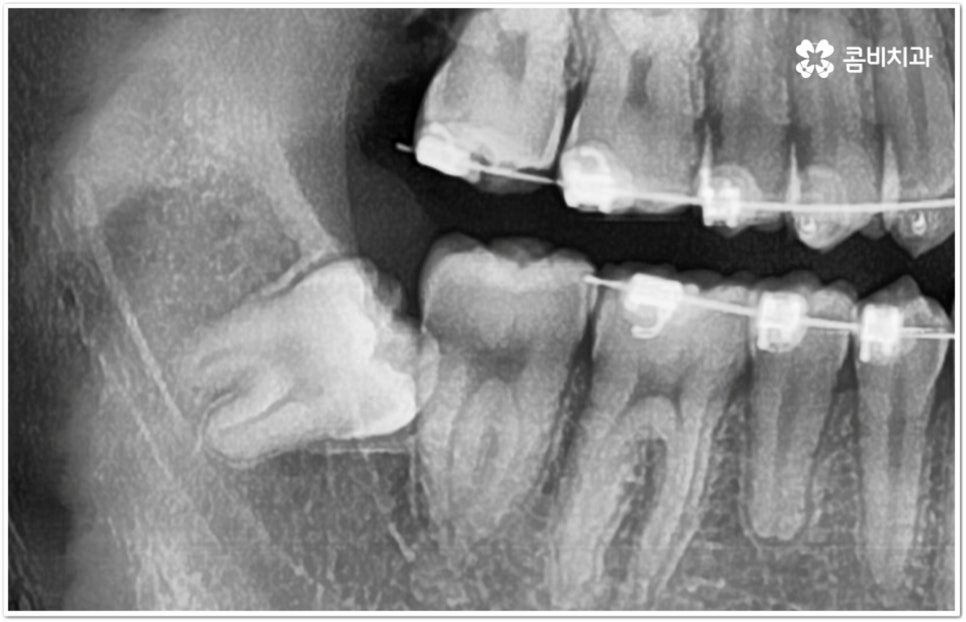

만약 똑바로 자라나고 관리가 용이하며 마주보는 대합치 역시 정상적으로 맹출되었다면 사랑니를 꼭 발치할 필요는 없을 거예요. 그러나 보통 사랑니는 사람의 치아 중에 가장 마지막에 나오는 치아라서 이미 구강 내 공간이 비좁은 상태이기 때문에 비스듬하게 자리를 잡고 일부분만 맹출이 되는 경우가 많이 있어요. 보통 머리가 앞쪽으로 기울어진 근심위로 자리잡는 케이스가 가장 많으며 그 밖에도 치아 머리가 뒤쪽으로 기울어져 있거나 혀쪽, 볼쪽으로 누운 케이스, 아예 옆으로 완전히 누운 케이스 등도 발견되고 있는데요.

잇몸에 반쯤 덮힌 채로 삐뚤게 나온 사랑니는 칫솔질을 제대로 하기 어렵고 위생 관리가 잘 되지 않아 주변 잇몸에 염증이 생기기 쉬우며 어금니까지 충치가 번질 위험이 높아지게 되어 구강 건강 관리 및 예방 차원에서 발치 처치를 해주실 필요가 있어요. 발치 난이도는 사랑니의 경사 각도와 방향 및 치아 뿌리의 길이와 개수, 사랑니 뒤쪽 턱 뼈의 각도 및 형태, 하치조 신경 또는 상악동까지의 거리 등에 따라서 달라질 수 있습니다.

이때 아래사랑니발치 의 경우 아래턱 부근을 지나가는 큰 신경인 하치조 신경을 건드리지 않고 조심스럽게 사랑니만 제거해야 하기 때문에 3D-CT 등 정밀 검진 기계를 통해 사랑니의 매복 위치, 깊이, 각도 등의 상태와 신경까지의 거리 등을 먼저 꼼꼼하게 파악한 후에 발치를 해 줄 필요가 있는데요. 만약 완전히 매복되어 있다면 사랑니 주변에 함치성 낭종이 발생할 수도 있는데 이로 인해 주변 치조골이 파괴되고 어금니 쪽으로 병변이 확산되면 결국 치아를 상실하게 되거나 턱뼈가 약해져서 작은 충격에도 부러지는 현상이 발생할 가능성도 있으므로 될 수 있는대로 치료 시기를 놓치지 않는 것이 중요한 포인트라고 할 수 있어요.